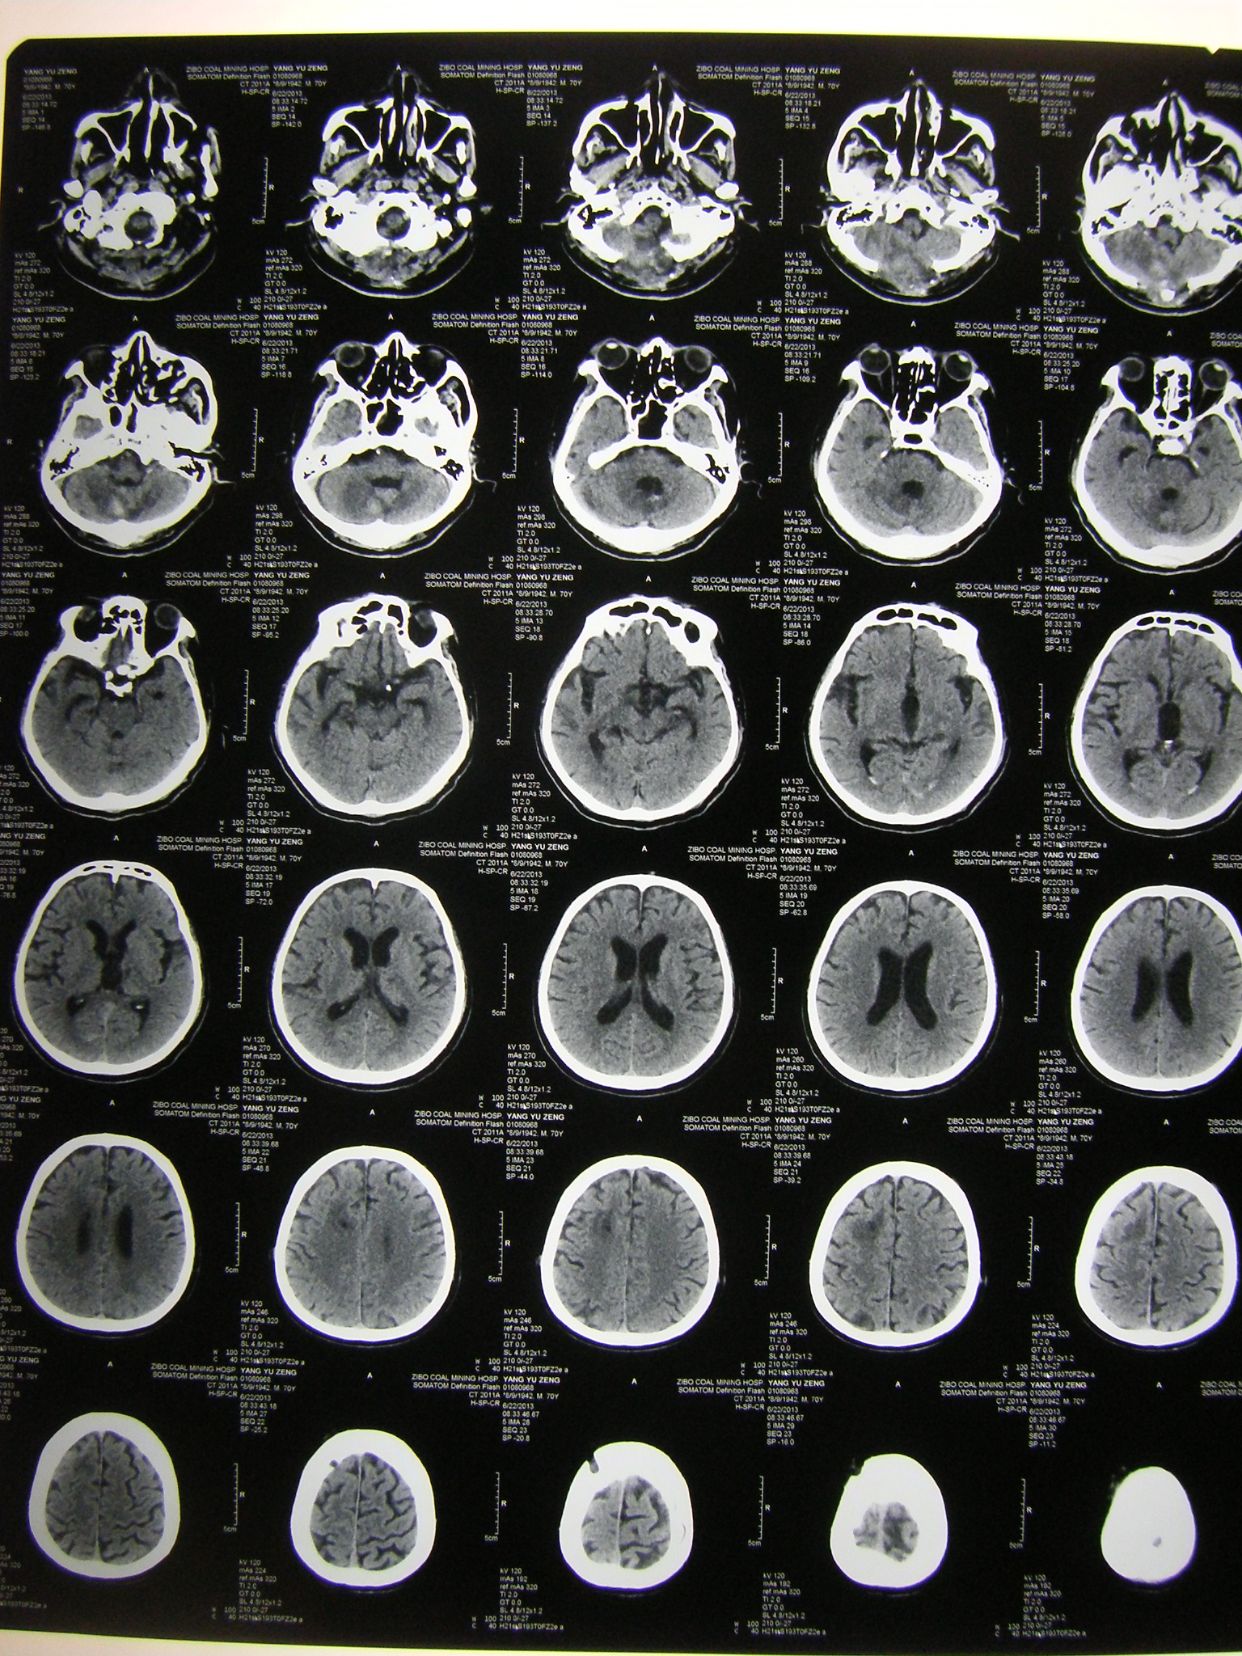

例1,患者男,70岁,突发意识不清1小时入院,有高血压等病史多年,深昏迷状,入院查体时出现呼吸停止,双瞳孔散大,立即气管插管,人工呼吸,建立静脉通道,应用甘露醇等。

CT显示小脑大量出血并破入全脑室,梗阻性脑积水,脑干受压变形,与家属沟通并签字后,急症行脑室引流术,后颅凹开颅血肿清除术,气管切开术。

术后3天CT复查示,血肿清除满意,基底池四脑室可见。

术后四周CT复查,脑沟回清楚,无脑积水征象,患者神志清,四肢可遵嘱动作,出院康复。